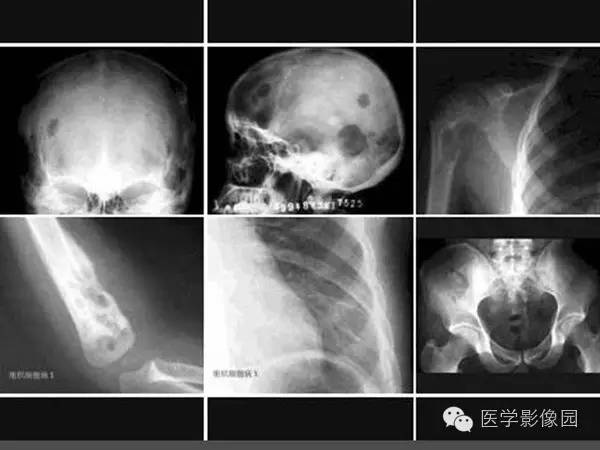

【病例】浆细胞性骨髓炎1例X线及CT影像表现